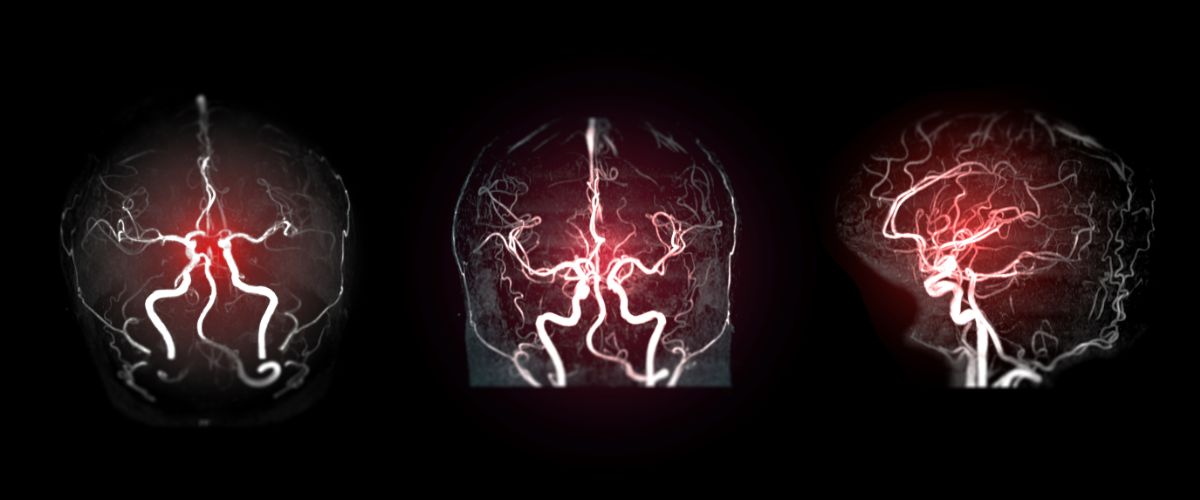

Un aneurisma es una dilatación anormal en la pared de una arteria, que puede ocurrir en diferentes partes del cuerpo, aunque es más común en los vasos sanguíneos del cerebro y el corazón. Esta expansión puede debilitar la pared del vaso y, en casos extremos, llevar a una ruptura, lo cual puede resultar en una hemorragia grave y potencialmente mortal.

- Aneurisma cerebral: Se produce cuando hay una dilatación en las arterias que irrigan el cerebro. Este tipo de aneurisma puede ser congénito o desarrollarse con el tiempo debido a factores como la hipertensión arterial o el tabaquismo.

En muchos casos, los aneurismas son asintomáticos y se descubren incidentalmente durante exámenes médicos de rutina. Sin embargo, en casos más graves o cuando ocurre una ruptura, los síntomas pueden ser evidentes. Algunos posibles síntomas de un aneurisma incluyen:

- Dolor repentino y severo: Un dolor intenso y repentino, a menudo descrito como «el peor dolor de cabeza de mi vida», puede ser indicativo de un aneurisma cerebral roto.

- Vigilancia y monitoreo: En muchos casos, los aneurismas pequeños y estables pueden no requerir intervención inmediata. En su lugar, el médico puede optar por monitorear el aneurisma regularmente mediante exámenes de seguimiento, como resonancias magnéticas o tomografías computarizadas.